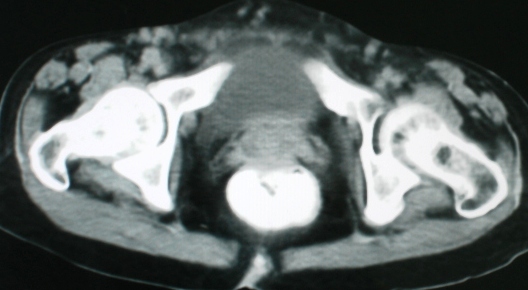

以下是引用zsl6918在2008-11-4 19:14:00的发言:[br]多发转移性改变,子宫改变不除外为原发灶